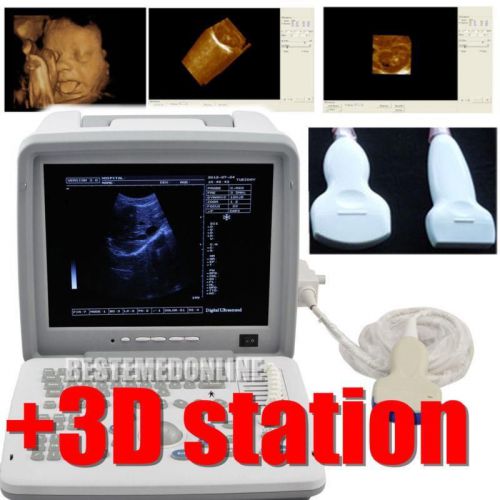

2 probes+3D Digital Ultrasound Scanner+3.5MHz Convex 7.5MHz Linear probe CE DFA

Portable Digital Ultrasound Scanner Machine + Convex + Linear Probe +3D BID BID

New Full Digital Portable Ultrasound Scanner With Convex+Linear (2 probes) +3D

2015 NEW Ultrasound Scanner machine+ CONVEX+External 3D workstation software kit